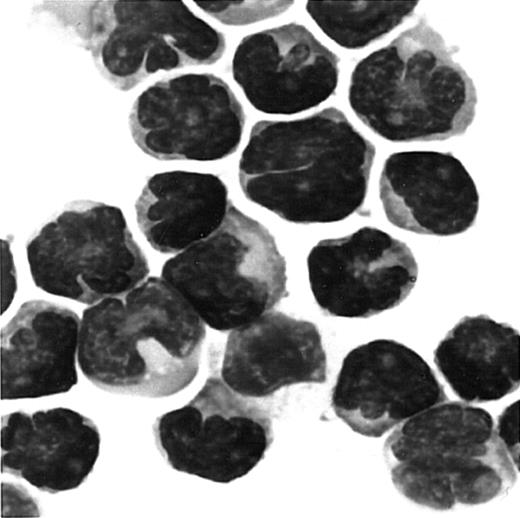

Since ATL cells have characteristic flowerlike nuclei, it is rather easy to identify ATL cells in blood smears. We therefore further carried out immunologic staining of CCR4 using routine blood smears from a total of 7 patients with ATL. Representative results are shown in Figure 4. Again, most ATL cases (6/7) were clearly stained positive for CCR4 (A, B, C: positive; D: negative).

Immunocytologic staining of CCR4 in blood smears.

Routine blood smears obtained from 4 patients with ATL (A-D) were stained for CCR4 as described in “Materials and methods.” Leukemic cells are positive (A, B, C) or negative (D) for CCR4. No staining was seen by an isotype-matched control mouse IgG (not shown).The slides were counterstained by hematoxylin and the original magnification was × 1000.

We next examined whether fresh ATL cells were capable of responding to the CCR4 ligands, TARC/CCL17 and MDC/CCL22,15 16 in a chemotactic assay using a Transwell plate. A total of 8 ATL cases (4 acute and 4 chronic) were studied. Representative results are shown in Figure5. We observed an efficient migration of PBMCs from all patients with ATL (8/8) toward TARC and MDC with a typical bell-shaped dose-response curve and an optimal concentration of about 1 nM. No such vigorous migration was observed by using fresh PBMCs from healthy adult donors in the present conditions. Thus, it is likely that the responding cells were mostly leukemic cells. To confirm this, we carried out a cytologic evaluation of cells migrated into the lower chambers. As shown in Figure 6, Giemsa staining of cytospin samples confirmed that migrated cells from PBMCs of patients with ATL were indeed mostly abnormal cells with characteristic flowerlike nuclei. Thus, fresh ATL cells expressing CCR4 are capable of efficiently responding to the CCR4 ligands TARC and MDC.

Giemsa staining of cells migrated to MDC/CCL22.

PBMCs were obtained from a patient with ATL. Cells migrated to MDC in chemotaxis chambers were collected and stained with Giemsa as described in “Materials and methods.” Original magnification, × 1000.